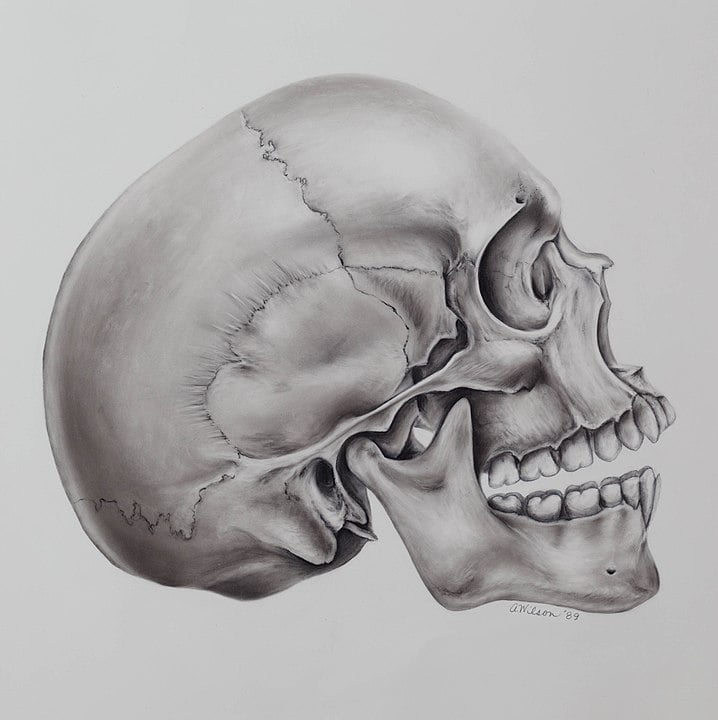

Lo más inmediato es empezar por practicar un montón la anatomía humana (a menos que lo tuyo sea la veterinaria, para lo cual también tendrías que checar libros pertinentes acerca del tema).

Si empiezas desde el trasfondo del artista, probablemente lo más recomendable sea checar libros de anatomía artística más especializados y de ahí escalar hacia publicaciones de corte mucho más médico, pues es ahí donde el dibujar ilustración médica entra en verdadero detalle acerca de todo tipo de sistemas, órganos y demás elementos de carácter biológico mucho más específicos.

- Habilidad artística con buen ojo para los detalles